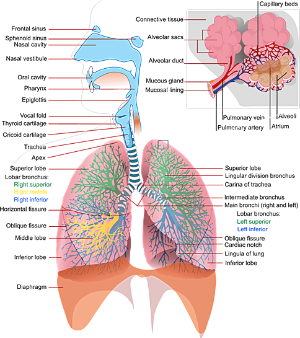

폐렴이란 주로 폐의 세기관지 이하 부분인 폐포에서 발생하는 염증을 말합니다. 이를 유발하는 병원 미생물들은 실제로 우리 생활환경에 존재하며, 때로는 우리 몸 안에서도 발견됩니다. 대부분의 폐렴은 이러한 미생물, 특히 세균이나 바이러스에 의해 발생하며, 드물게는 곰팡이로 인한 감염도 있습니다.

폐렴은 폐 기관지나 폐포에 체액이 축적되어 호흡곤란이나 심한 기침을 유발하며, 초기 증상은 일반적인 감기와 유사하므로 주의가 필요합니다. 폐렴의 기침 증상은 감기나 독감과 크게 다르지 않을 수 있지만, 녹색 점액을 동반하는 경우가 있습니다. 이러한 증상은 방치하면 폐렴이 악화될 수 있으므로, 단순한 기침이라도 반드시 의료 기관에서 진단을 받는 것이 중요합니다. 특히 노인이나 유아의 경우 더욱 심각한 상황을 초래할 수 있으므로, 주의가 필요합니다.

폐렴은 폐 기능을 저하시켜 호흡곤란을 유발합니다. 이는 폐가 충분한 산소를 공급하지 못하게 되어 호흡이 힘들어지는 증상이며, 이로 인해 환자는 숨쉬기가 힘들고 얕아지는 느낌을 받을 수 있습니다. 또한, 가슴 통증과 함께 호흡곤란이 더욱 심해질 수 있습니다.

일반적으로 폐렴 환자는 숨 가쁨을 경험하며, 이는 종종 기관지염으로 오해받을 수 있습니다. 폐렴의 초기 증상은 일반 감기나 기관지염과 유사하기 때문에 치료 후에도 증상이 개선되지 않는다면 폐렴을 의심해야 합니다. 폐렴으로 인한 폐 감염은 체액과 고름이 쌓이게 하여 통증을 유발하고, 이는 산소가 폐포에서 혈류로 이동하는 것을 어렵게 만듭니다. 결과적으로 숨 가쁨이 발생하며, 이는 복부 통증과 압박감을 동반할 수 있습니다. 이러한 증상은 숨 가쁨과 가슴의 쌕쌕거림을 유발하며, 이는 호흡곤란으로 이어질 수 있습니다.